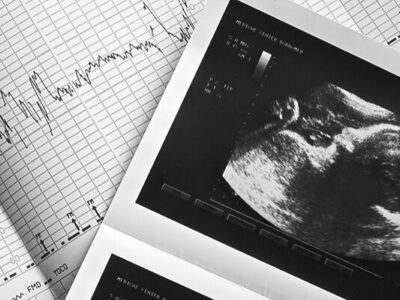

به گزارش ایرانیان تحلیل – مرضیه وحید دستجردی در گفتوگو با ایسنا تأکید کرد که غربالگری در دوران بارداری، بخشی از فرآیند رسمی نظام سلامت کشور است و همچنان در مراکز درمانی انجام میشود.

به گفته دبیر ستاد ملی جمعیت، غربالگری از پشتوانه قانونی برخوردار است و بهطور نظاممند تحت نظارت وزارت بهداشت انجام میشود. این برنامه همچنان بخشی از سیاستهای سلامت مادر و جنین است.